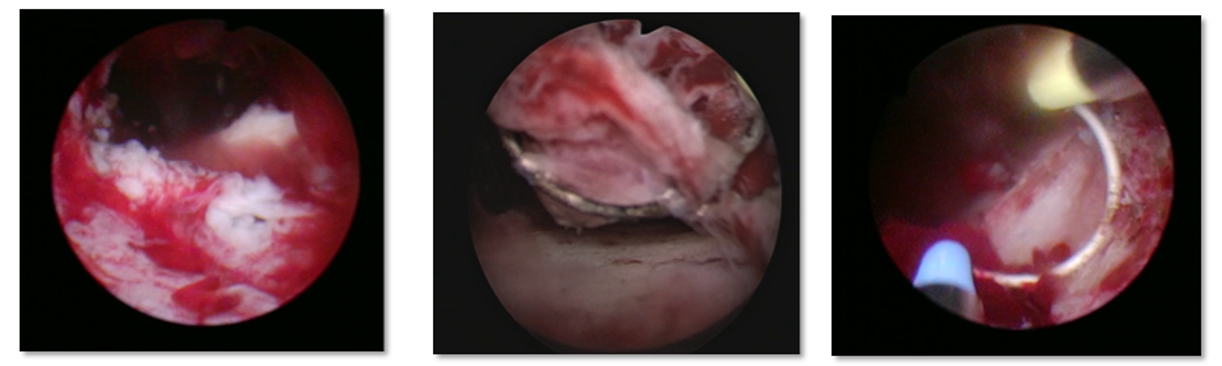

아쿠아 블레이션 수술 과정

초음파와 내시경을 동시에 실시간으로 확인하며 절제할 조직과 보존할 조직을 정확히 설계

설계에 맞춰 정확하게 고수압 워터젯을 분사하여 비대조직을 제거

출혈 부위를 지혈하고 절제 범위를 면밀히 확인한 뒤 수술 마무리